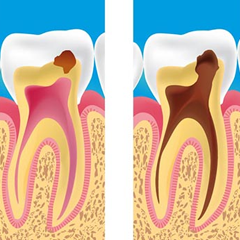

Restaurativa Estetica

La Restaurativa Estetica è quella branca dell’Odontoiatria che si occupa della cura dei denti cariati, delle procedure per l’eliminazione della carie.

Endodonzia

L’Endodonzia è la branca dell’Odontoiatria che si occupa delle terapie dell’endodonto, ovvero dello spazio all’interno degli elementi dentali, dove è contenuta la polpa dentaria.